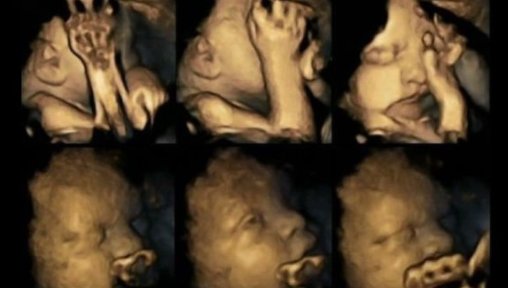

Visai neseniai medikai paviešino ultragarso nuotrauką, kuri parodo, kaip vaisius reaguoja į tai, kad jo mama rūko.

Britų mokslininkas palygino rūkančių ir nerūkančių nėščių moterų ultragarso nuotraukas. Rezultatai parodė, kad rūkančių moterų gimdoje esantis dar negimęs vaikutis tarsi bando slėpti savo veidą.